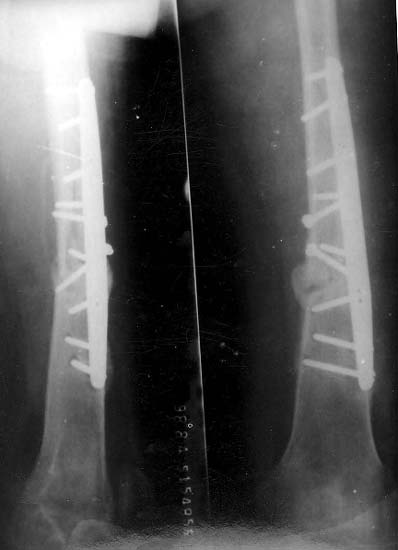

股骨骨折不愈合患者,经注射骨生长因子和骨髓细胞,6个月后骨折愈合